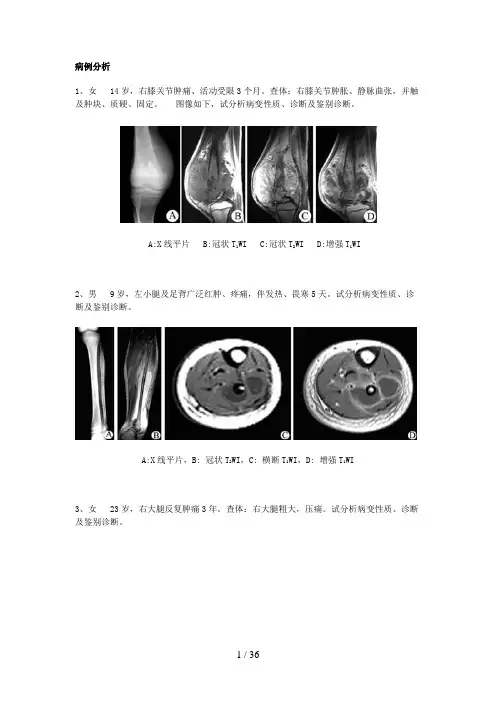

病例分析1、女 14岁,右膝关节肿痛、活动受限3个月。

查体:右膝关节肿胀、静脉曲张,并触及肿块、质硬、固定。

图像如下,试分析病变性质、诊断及鉴别诊断。

A:X线平片 B:冠状T1WI C:冠状T2WI D:增强T1WI2、男 9岁,左小腿及足背广泛红肿、疼痛,伴发热、畏寒5天。

试分析病变性质、诊断及鉴别诊断。

A:X线平片,B: 冠状T2WI,C: 横断T1WI,D: 增强T1WI3、女 23岁,右大腿反复肿痛3年。

查体:右大腿粗大,压痛。